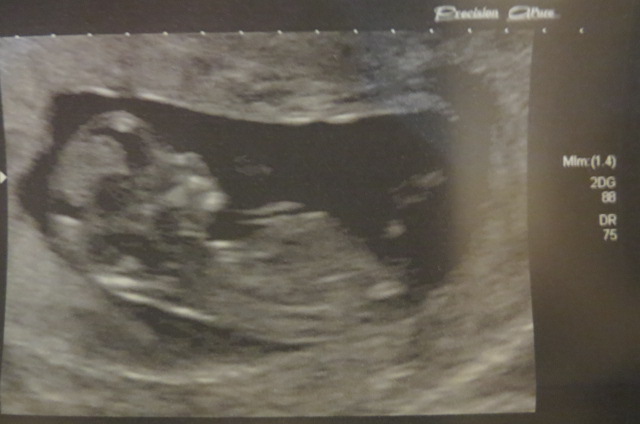

My friend had done an ultrasound at 16 weeks, 2 days and it wasn't very clear... I rewatched my video and caught this!

Attachment 29061

IT'S A BOY!!!

Attachment 29184